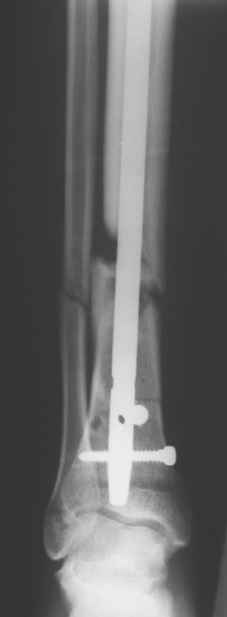

Перелом большеберцовой кости почти околосуставный, могут потребоваться дополнительные меры для восстановления оси (отклоняющие спицы или винты), и запирающих винтов в дистальный отломок желательно побольше. Задний край не сломан ли там, не разобрал по этим снимкам.

Сегодня прооперировали без открывания. Хотел-бы услышать комментарии по поводу послеоперационной нагрузки.

Учитывая изначальные снимки и то. что сделали , не открывая - весьма достойно. Доктор Коган прав - перелом немного перерастянут ( что хорошо видно по фибуле), а перерастянутые переломы большеберцовой срастаются очень плохо. Поэтому я бы обязательно дал раннюю динамизацию - на 6 неделях ( когда можно не опасаться малротации) разблокировал бы проксимальный фрагмент полностью и начал бы нагружать ногу. Будьте готовы к остеотомии ( или остеоэктомии участка) малоберцовой чеерз несколько месяцев- уж слишком хорошо стоит - очень вероятно, что срастется рано и будет держать большеберцовую перерастянутой

вдогонку - до разблокирования нагружать противопоказано - все, чего добьетесь - погнете шурупы. причем, если погнете дистальные ( как обычно бывает) - гвоздь провалится в сустав. Нагружайте птолько после проксимальной динамизации, когда будете уверены, что гвоздь поднагрузкой будет смещаться вверх, а не вниз

По представленым снимкам, "контакт" между отломками не очень =(. А боковой проекции нет?

Уважаемый Юрий Алексеевич, сложный перелом, смелое решение, хорошее исполнение и, надо надеяться, хороший будет результат. Но, что бы он (результат) был достойным, надо подготовиться и к худшему. В чём, с моей точки зрения, главная проблема, которую придётся решать. Да, вне всякого сомнения, система нуждается в ранней динамизации в совокупности с ранней же нагрузкой. В данном случае, мне кажется, можно было бы решиться и на первичную динамизацию, то есть проксимально блокировать гвоздь только через овальное отверстие, отказавшись от введения винта через круглое отверстие. В этом случае и нагрузку можно было бы начать раньше, чем через 6 недель, не опасаясь перелома дистальных винтов. Однако, имеющееся лёгкое вальгусное смещение может прогрессировать в случае полной нагрузки, которую, как справедливо отмечено форумом, требует имеющееся стояние отломков. И предотвратить дальнейшее вальгирование может достаточная наружная опора, которая возможна при хорошем стоянии поперечного перелома малоберцовой кости даже без его внутренней фиксации, как раз как в представленном случае. А, в то же самое время, раннее сращение малоберцовой кости может препятствовать консолидации большеберцовой кости. То есть, своеобразный замкнутый круг может получиться. И так, главная проблема, с которой мы можем здесь столкнуться зависит не от диастаза между основными фрагментами, и не от вальгуса, и не от хорошей репозиции поперечного перелома малоберцовой кости - а от совокупности всех трёх факторов.

Поэтому, мне кажется, пациент будет требовать постоянного внимания на этапе реабилитации. И, помимо темпа консолидации, контроля положения дистального конца гвоздя из за опасения пенетрации сустава, не меньшего внимания будет заслуживать и угловое стояние отломков. Мне кажется, что в случае отсутствия формирования периостальной мозоли в допустимые сроки вряд ли будет целесообразным выполнение остеотомии малоберцовой кости. Это, равно как и хотя бы незначительное усугубление вальгуса может послужить основанием для переустановки гвоздя. Но - это худший вариант, который, я надеюсь, не случится. Но о котором нужно помнить.

АВ> Однако, имеющееся лёгкое вальгусное смещение

Что-то не то тут с вальгусом. По положению гвоздя не должно его быть.

Увидеть бы сравнительные снимки дистальных отделов голеней, может статься, симметричный голеностопный сустав выглядит так же.

Насчет диастаза - конечно, надо динамизировать хоть сегодня, ждать 6 недель я бы не стал. И боковой снимок бы увидеть.

Выкручивать проксимальный статический винт можно, если еще не выкрутили) Нагрузка - ногу на пол ставить можно, без переноса веса тела на нее. А с вальгусом действительно интересно на снимке выходит, может ротационное смещение осталось? Любопытно на боковую взглянуть и на ногу без рентгена